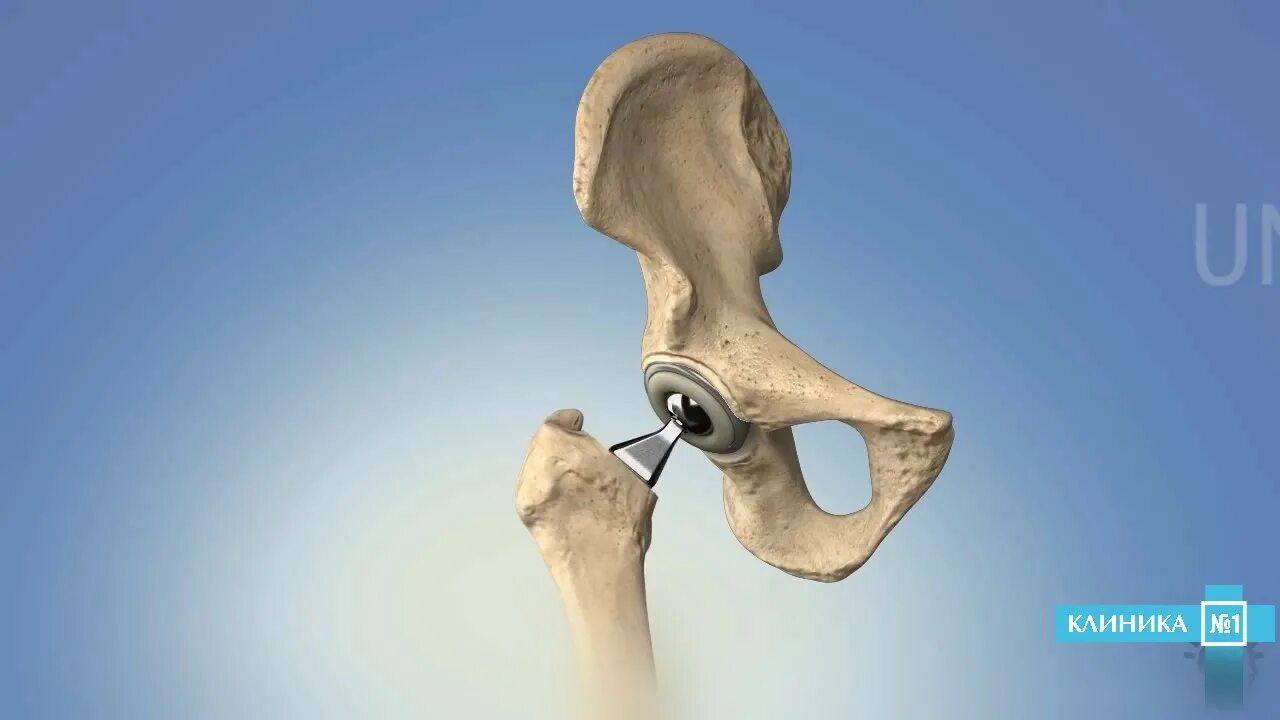

Эндопротезирование тазобедренного сустава видео